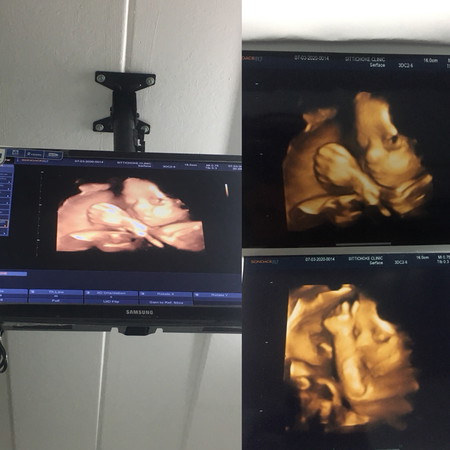

ดิ้นเก่งมาก?

31 พ.ค ดิ้นเก่งถีบเก่งแรงขึ้นเรื่อยๆ ใจอยากเห็นแล้ว ได้แต่รออออ ❤️🤣✌🏻

7พ.ค. อยากให้ถึงเร็วๆเหมือนกันค่ะ อยากเห็นน่าเค้าใจจะขาด

บ้านนี้กำหนดผ่า28พ.ค คะ ผช.คะ ดิ้นดีเหมือนกันเลยคะ 😍😍

14 พฤษภาคม ดิ้นเก่งมากเหมือนกันค่ะ เพศหญิงจร้

พ.ค เหมือนกันค่ะ อยากเห็นหน้าลูกจะแย่แล้ว

เวลาเราเห็นแล้วเรารู้ดีมีกำลังใจมากค่ะ